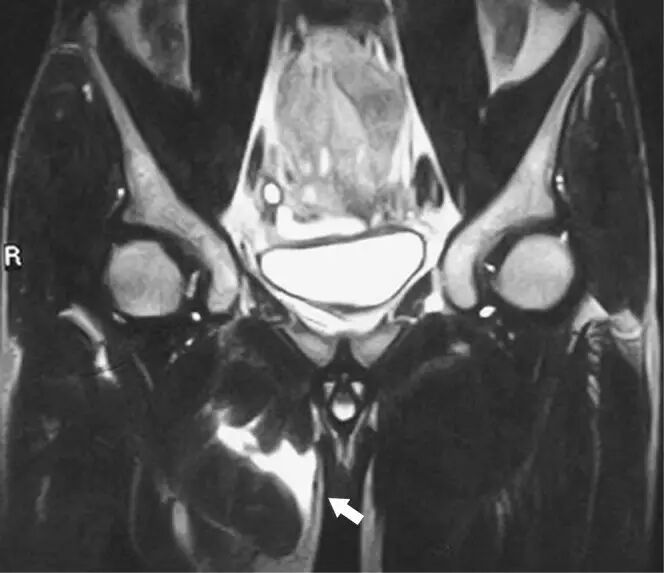

图20.肌包虫病感染在一个46岁的农夫,肌肉的疼痛肿胀的近端大腿和臀部。冠状脂肪抑制T2加权磁共振成像显示左大腿和髋部肌肉的包裹性高信号--寄生虫包囊(箭头)。

![]()